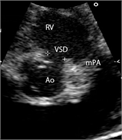

1. 心室中隔欠損は、欠損孔の部位により、膜性周囲部(perimembranous)、筋性部(muscular)、漏斗部または肺動脈弁下部(subarterial)に分類され、自然歴、手術適応が各々異なるため、部位診断は重要である。

1. 心室中隔欠損は自然閉鎖する場合もあるが、心不全症状を有する、あるいは肺高血圧を合併する場合、漏斗部欠損で大動脈弁の逆流を呈する場合は、外科手術の適応となる(推奨度1)。Eisenmenger症候群を呈すると手術適応がなくなるので、その前に適切な治療時期を逃さないことが大切である。